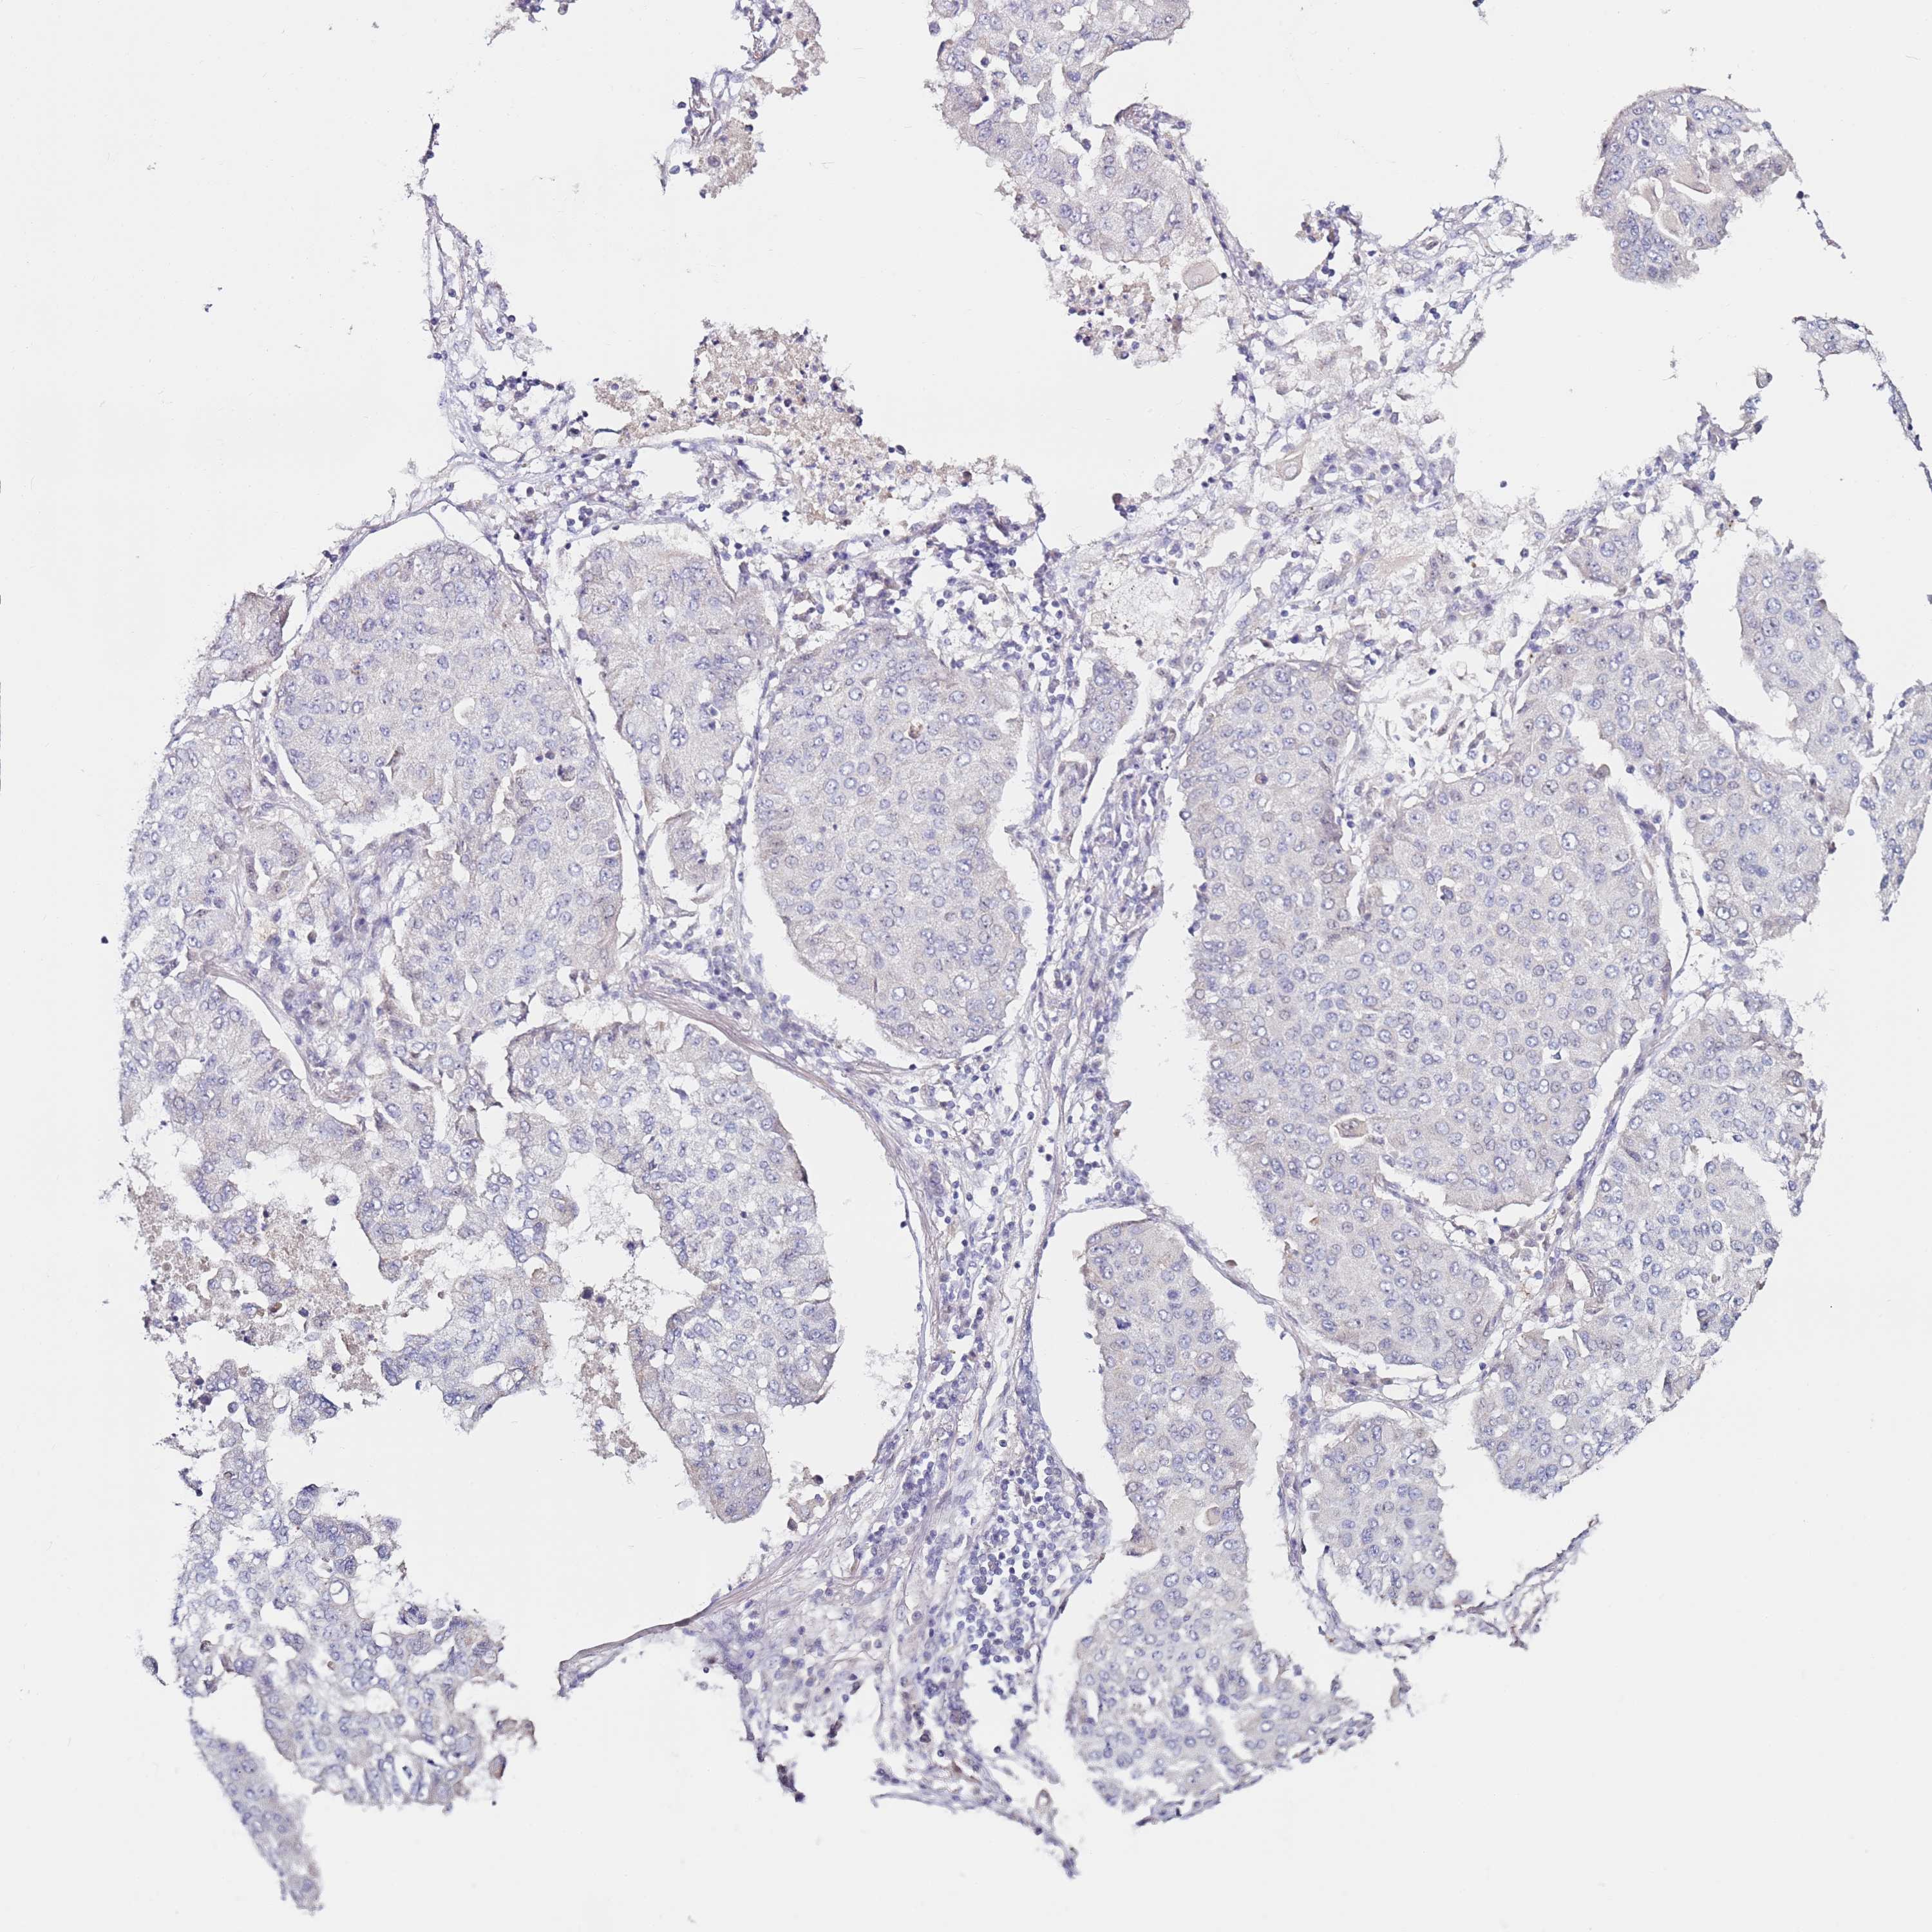

CANCER LUNG CANCER Show tissue menu

LUAD TCGA LUAD VALIDATION LUSC TCGA LUSC VALIDATION PROTEIN LUAD CPTAC PROTEIN LUSC CPTAC PROTEIN EXPRESSION

ANTIBODIES

AND

VALIDATION